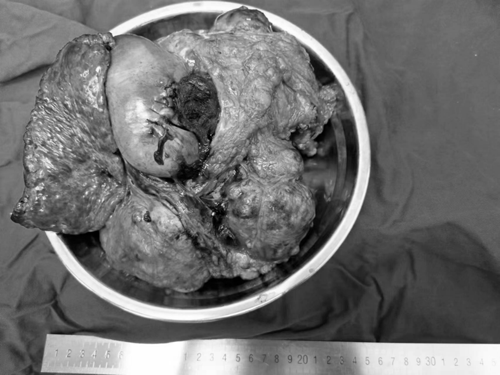

| Hình ảnh khối u ung thư gan lấy từ cơ thể bệnh nhân. Ảnh: Sohu |

Nhận định về ca mổ, bác sĩ Zhou Zhi cho biết đây là ca có độ khó cao. Khối u kích thước quá lớn, độ dính trong ổ bụng cao, chèn ép các cơ quan xung quanh, có nguồn cung cấp máu dồi dào và không gian mổ rất hẹp. Ê kíp vô cùng thận trọng, tập trung cao độ mới có thể loại bỏ thành công khối u 5kg ra khỏi bụng bệnh nhân.